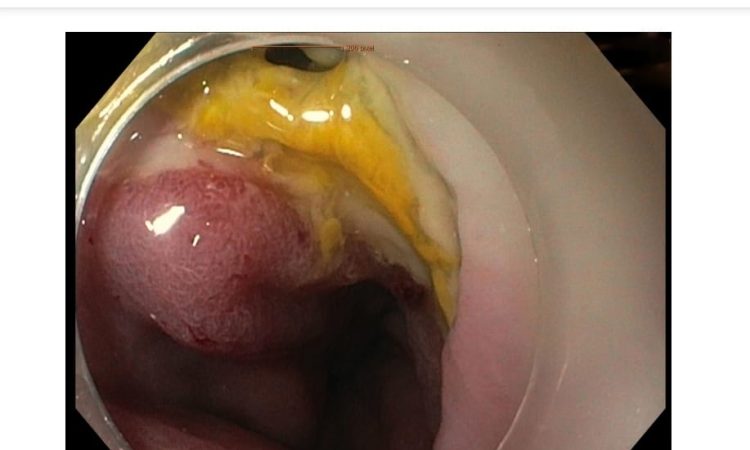

ಮಣಿಪಾಲ :ಮಣಿಪಾಲದ ಕಸ್ತೂರ್ಬಾ ವೈದ್ಯಕೀಯ ಕಾಲೇಜು ಮತ್ತು ಆಸ್ಪತ್ರೆಯ ಗ್ಯಾಸ್ಟ್ರೋಎಂಟರಾಲಜಿ ಮತ್ತು ಹೆಪಟಾಲಜಿ ವಿಭಾಗವು ಮೊದಲ ಬಾರಿಗೆ ಅನ್ನನಾಳದ ರಂದ್ರಕ್ಕೆ ಮತ್ತು ಅನಾಸ್ಟೊಮೊಟಿಕ್ ಸೋರಿಕೆ ಪ್ರಕ್ರಿಯೆಗೆ ಅಪರೂಪದ ಎಂಡೋಸ್ಕೋಪಿ ಸ್ಪಾಂಜ್ (ಎಂಡೋವಾಕ್) ಚಿಕಿತ್ಸೆಯನ್ನು ನಡೆಸಿತು, ಇದು ಕರ್ನಾಟಕದಲ್ಲಿ ಮೊದಲ ಬಾರಿಗೆ. ಶಸ್ತ್ರಚಿಕಿತ್ಸಾ ಅನಾಸ್ಟೊಮೊಸಿಸ್ ವಿಫಲವಾದಾಗ ಮತ್ತು ಶಸ್ತ್ರಚಿಕಿತ್ಸಾ ಸಂಪರ್ಕದಿಂದ ಮರುಸಂಪರ್ಕಿತ ದೇಹದ ಚಾನಲ್ನ ವಿಷಯಗಳು ಸೋರಿಕೆಯಾದಾಗ ಅನಾಸ್ಟೊಮೊಟಿಕ್ ಸೋರಿಕೆ ಸಂಭವಿಸುತ್ತದೆ. ಇದು ಕರುಳಿನ ಛೇದನದ ಶಸ್ತ್ರಚಿಕಿತ್ಸೆಯ ಅತ್ಯಂತ ಗಂಭೀರ ತೊಡಕುಗಳಲ್ಲಿ ಒಂದಾಗಿದೆ.

51 ವರ್ಷದ ವ್ಯಕ್ತಿಗೆ ಅನ್ನನಾಳದ ಕ್ಯಾನ್ಸರ್ ಇರುವುದು ಪತ್ತೆಯಾದ ನಂತರ ಶಸ್ತ್ರಚಿಕಿತ್ಸೆ ನಡೆಸಿ ನಂತರ ಕೀಮೋಥೆರಪಿ ಮೂಲಕ ಚಿಕಿತ್ಸೆ ನೀಡಲಾಯಿತು. ಒಂದು ವಾರದ ನಂತರ ಅವರಲ್ಲಿ ಅನಾಸ್ಟೊಮೊಟಿಕ್ ಡಿಹಿಸೆನ್ಸ್ನೊಂದಿಗೆ ಮೆಡಿಯಾಸ್ಟಿನಿಟಿಸ್ ಅಭಿವೃದ್ಧಿಯಾಯಿತು. ಇದನ್ನು ಸರಿಪಡಿಸಲು ವೈದ್ಯರು ಮತ್ತೊಂದು ಶಸ್ತ್ರಚಿಕಿತ್ಸೆಯ ಅವಶ್ಯಕತೆಯ ಬಗ್ಗೆ ಆಲೋಚಿಸಿದರು. ಆದರೆ ರೋಗಿಯ ಸಾಮಾನ್ಯ ಸ್ಥಿತಿಯು ಕಳಪೆಯಾಗಿತ್ತು ಮತ್ತೊಂದು ಶಸ್ತ್ರಚಿಕಿತ್ಸೆ ಕಷ್ಟವಾಗಿತ್ತು. ಗ್ಯಾಸ್ಟ್ರೋಎಂಟರಾಲಜಿ ಮತ್ತು ಹೆಪಟಾಲಜಿ ವಿಭಾಗದ ಮುಖ್ಯಸ್ಥರಾದ ಡಾ ಶಿರನ್ ಶೆಟ್ಟಿ ಮತ್ತು ಡಾ ಬಾಲಾಜಿ, ಸರ್ಜಿಕಲ್ ಆಂಕೊಲಾಜಿ ವಿಭಾಗದ ಮುಖ್ಯಸ್ಥರಾದ ಡಾ ನವೀನ ಕುಮಾರ್, ಪ್ಲಾಸ್ಟಿಕ್ ಸರ್ಜರಿ ವಿಭಾಗದ ಸಹಾಯಕ ಪ್ರಾಧ್ಯಾಪಕ, ಡಾ ಜೋಸೆಫ್ ಥಾಮಸ್ ವೈದ್ಯರ ತಂಡವು ಎಂಡೋಸ್ಪಾಂಜ್ / ವ್ಯಾಕ್ಯೂಮ್ ಥೆರಪಿ ಎಂಬ ನವೀನ ಚಿಕಿತ್ಸೆಗೆ ಹೋಗಲು ನಿರ್ಧರಿಸಿದರು. ಇಲ್ಲಿ ಎಂಡೋಸ್ಕೋಪಿಯ ಮೂಲಕ ಎಂಡೋಸ್ಕೋಪಿ ಮೂಲಕ ಸ್ಪಾಂಜ್ ಅನ್ನು ಮೆಡಿಯಾಸ್ಟಿನಮ್ ಕುಳಿಯಲ್ಲಿ ಇರಿಸಲಾಯಿತು, ಇದು ನೈಸರ್ಗಿಕವಾಗಿ ಮತ್ತು ಯಾವುದೇ ಯಾವುದೇ ಶಸ್ತ್ರಚಿಕಿತ್ಸೆಯಿಲ್ಲದೆ ದೋಷವನ್ನು ಮುಚ್ಚಲು ಸಹಾಯ ಮಾಡಿತು. ಮೂರು ವಾರಗಳ ನಂತರ ರೋಗಿಯು ನೇರವಾಗಿ ಬಾಯಿಯ ಮೂಲಕ ತಿನ್ನಲು ಸಾಧ್ಯವಾಯಿತು. ಇದು ದಕ್ಷಿಣ ಭಾರತದ ಈ ಭಾಗದಲ್ಲಿ ರೋಗಿಗಳಿಗೆ ಚಿಕಿತ್ಸೆಗೆ ಮಾಡಿದ ಮೊದಲ ವಿನೂತನ ವಿಧಾನವಾಗಿದೆ ಮತ್ತು ಇದು ಕಡಿಮೆ ವೆಚ್ಚದ ಮತ್ತು ಸುರಕ್ಷಿತ ವಿಧಾನವಾಗಿದೆ ಎಂದು ಡಾ ಶಿರನ್ ಶೆಟ್ಟಿ ತಿಳಿಸಿದ್ದಾರೆ.